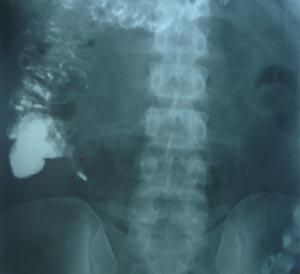

Filling defect may be suggestive of appendicolith. There is high correlation of presence of appendicolith & appendicitis. But better way of imaging will be ultrasonography or CT, which can locate surrounding pathology with condition of caecum.